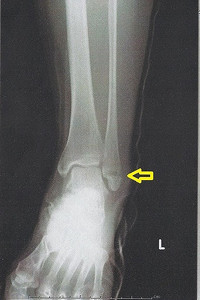

足首捻挫と骨折の違いとは?

さて、なぜ同じように足を捻ったのに捻挫で済む場合と骨折してしまう場合があるのでしょうか?

そもそも、怪我は体が耐えられる以上の力がかかった時に生じます。そして、体のどこかが耐えきれずに破綻するのですが、それが靭帯であれば捻挫、骨であれば骨折となります。

ちょっとした力の方向やかかり方によって捻挫になる場合と骨折になる場合があるのです。

ですから、ちょっとでもおかしいなと思ったら、

病院でレントゲンを撮ってもらうのが最も早くて正確な方法です。